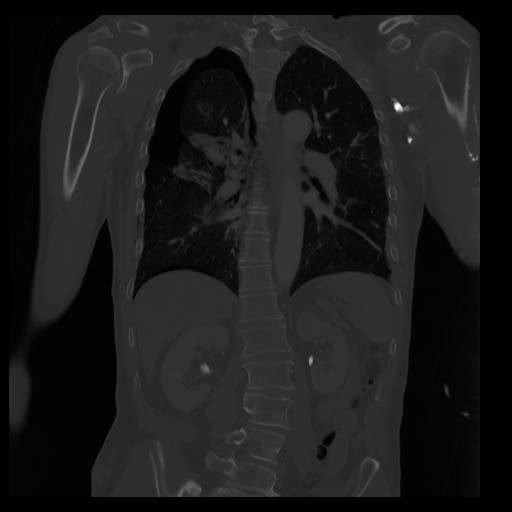

29 CUERPO,CE,Coronal,3.000,CUERPO,Coronal,